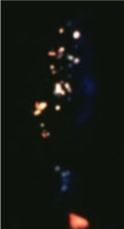

christmas tree cataract (myotonic dystrophy)